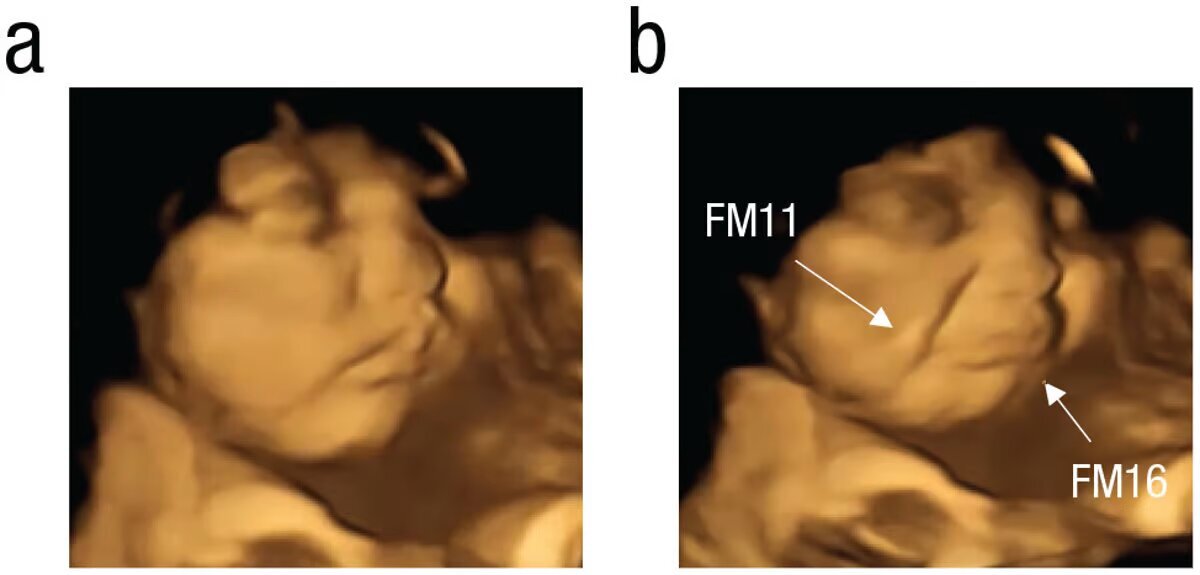

На удивительных кадрах полученных при помощи УЗИ, хорошо видно, как будущие детки с отвращением морщат лица через несколько минут после того, как мать съела горькую капусту, или улыбаются, когда до них добегает сладкий вкус моркови.

Иллюстрация Beyza Ustun et al. / Psychological Science, 2022.

Чтобы проверить гипотезу, исследователи использовали так называемую 4D-ультразвуковую технологию, ценному способу визуализации движений плода с высокой детализацией. Участие в эксперименте приняли 100 матерей, все в последнем триместре беременности.

Невероятные результаты показали, что у деток, которым "скормили горькую капусту", было больше реакций в виде "плачущего лица" по сравнению с плодами, которым "скормили" сладкую морковь. Последние чаще меняли выражение лица на "смеющиеся лица".

В контрольной группе плод более последовательно демонстрировал нейтральные лица, так как не подвергался воздействию какого-либо вкуса. (Тут поясним, что дети в утробе могут "выдавать эмоцию" и по другим поводам,

как бы спонтанно улыбаясь.)